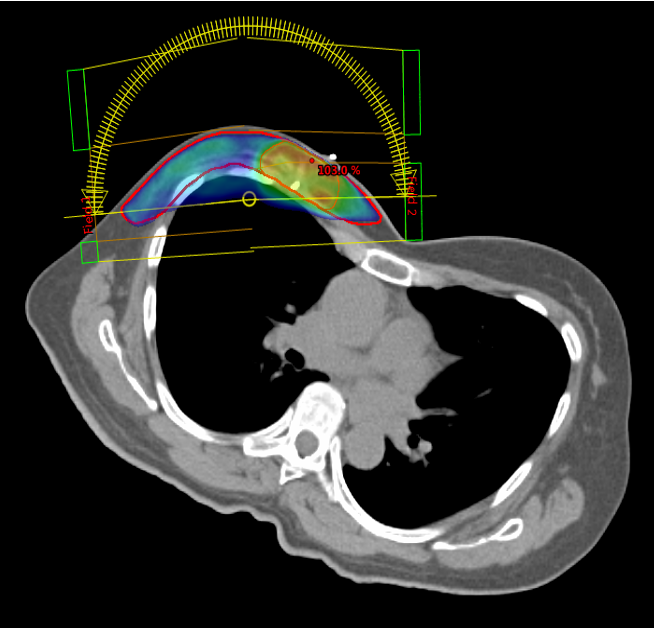

Brustkrebs Bestrahlung Schräglage

Die 3D-konformale Strahlentherapie (3D-CRT) ermöglicht es, einen Tumor durch verschiedene Bestrahlungsfelder mit unterschiedlichen Einstrahlwinkeln zu behandeln. Dabei wird das Tumorgebiet präzise bestrahlt, während die angrenzenden Organe und Risikostrukturen wie Herz, Lunge, Darm, Harnblase, Augen, Speicheldrüsen, Hirnstamm oder Rückenmark bestmöglich geschont werden.

In vielen Bereichen der Medizin können mit dieser Methode hervorragende Behandlungsergebnisse erzielt werden.

Die 3D-CRT stellt die Grundlage jeder strahlentherapeutischen Therapie dar.